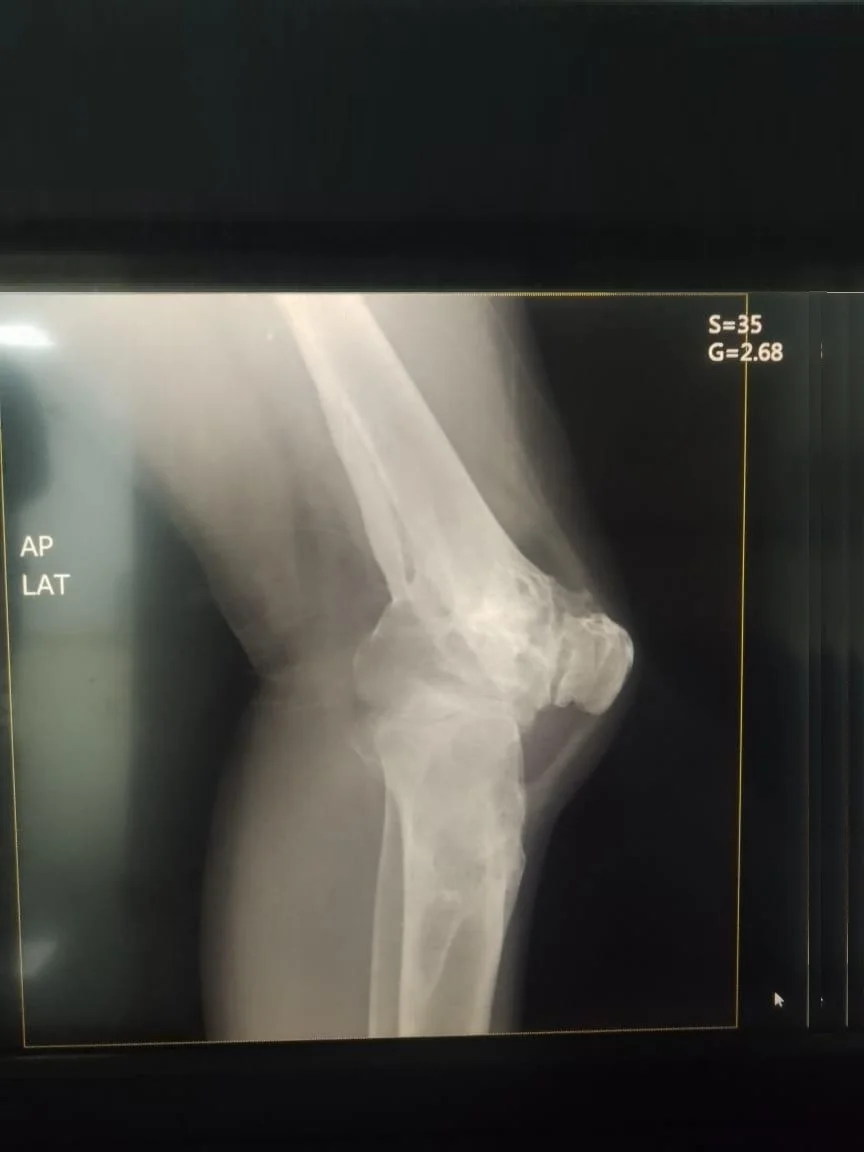

Antes Radiografía preoperatoria de fractura de tibia y osteoartrosis de rodilla

Después Radiografía postoperatoria de reemplazo articular de rodilla tras fractura de tibia

Traumatología

Reemplazo articular

Fractura de Tibia

• Perfil del Paciente: Masculino, 50 años.

• Historia Clínica: Antecedentes de 25 años de evolución con dolor crónico y pérdida de movilidad.

• Diagnóstico: Osteoartrosis secundaria a fractura de rodilla antigua.

• Resultado (Caso 2024): Intervención exitosa con recuperación completa. Actualmente el paciente presenta una evolución óptima y retorno a su vida cotidiana.